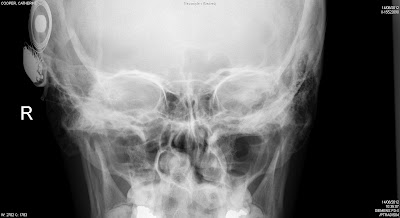

[UPDATE: Since I wrote this, the switch-on happened, and went smoothly. I’ll write a brief summary of the day shortly and upload some photos, but need to gather my thoughts first. Before then, and over the coming days, I’m going to list all the sounds I’m hearing for the first time. And below is an X-ray of my head, following the operation to insert my implant. You can see the implant fixed to my skull, and the 12 individual electrodes on the curled wire which sits inside my cochlea.]